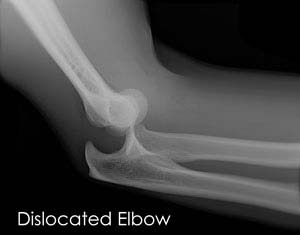

The elbow is a hinge joint made up of 3 bones – humerus, radius and ulna. The bones are held together by ligaments to provide stability to the joint. Muscles and tendons move the bones around each other and help in performing various activities. Elbow dislocation occurs when the bones that make up the joint are forced out of alignment.

To diagnose elbow dislocation your doctor will examine your arm. Your doctor will check the pulses at the wrist and will evaluate the circulation to the arm. An X-ray is necessary to determine if there is a break in the bone. An arteriogram, an X-ray of your artery can be helpful to know if the artery is injured.